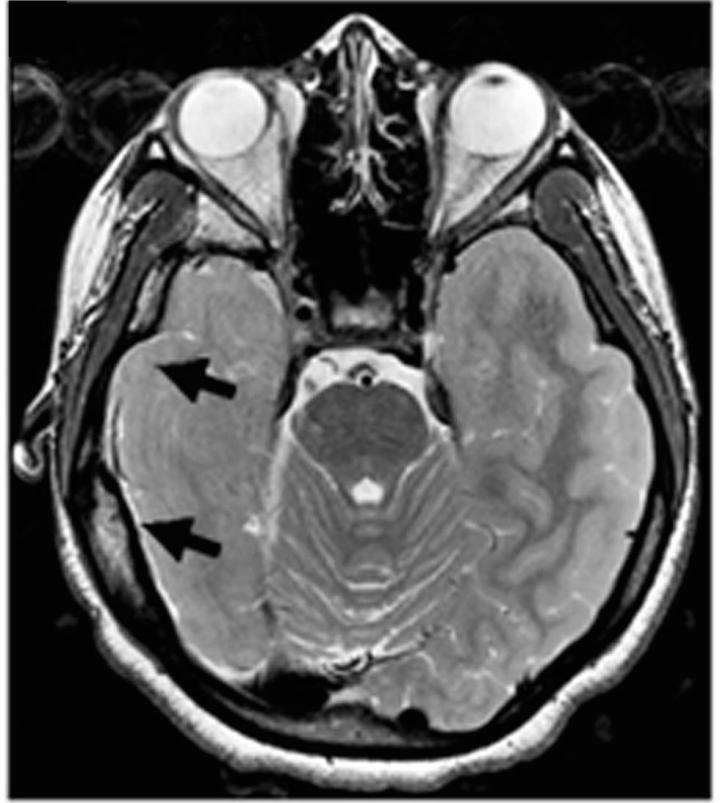

When patients with epilepsy don't experience enough benefit from current medications, doctors sometimes treat the disorder by surgically removing the area where seizures arise. Liu, who was an investigator at the Children's National Medical Center in Washington DC during the research, decided to study tissues removed from eight patients with either focal cortical dysplasia or tuberous sclerosis complex to see if she and her co-authors could discern what might be going awry at the molecular level. As an experimental control, they used "healthy" tissues from the patients when those needed to be removed to allow access to the seizure-producing sites.

The first step was to analyze the "transcriptome" of the tissues, or the various RNA transcribed from DNA to produce proteins. They found some significant differences. In particular they measured a notable decrease in the expression of RNA for CLOCK compared to controls. Further analysis including in tissues from more patients with other forms of epilepsy also showed that CLOCK RNA and protein were often significantly lacking in both in excitatory and inhibitory neurons in affected brain regions.